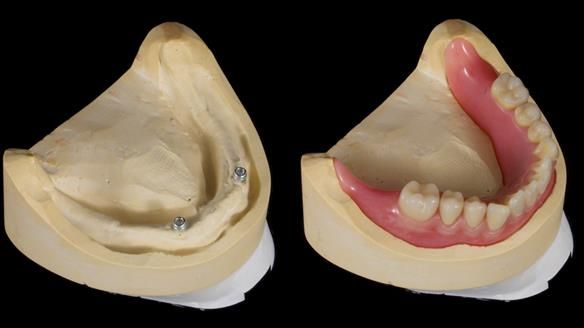

2. The upper denture, horseshoe-shaped and metal-reinforced, rocks on the ridge, causing wear on Locator abutments and a fractured upper right tooth.

The detailed clinical situation and treatment process are outlined below, with clinical work provided by me and technical work by Rowan Garstang. New complete implant supported complete dentures were made. The new upper denture had ‘almost’ full palatal extension for the non-splinted implants following ITI guidelines. A decision was reached to retain the worn Kerator attachments, as their removal could potentially accelerate implant failure. The treatment spanned five visits for denture fitting and one review. Alisdair expressed great satisfaction with the treatment, noting a significant enhancement in his overall quality of life.